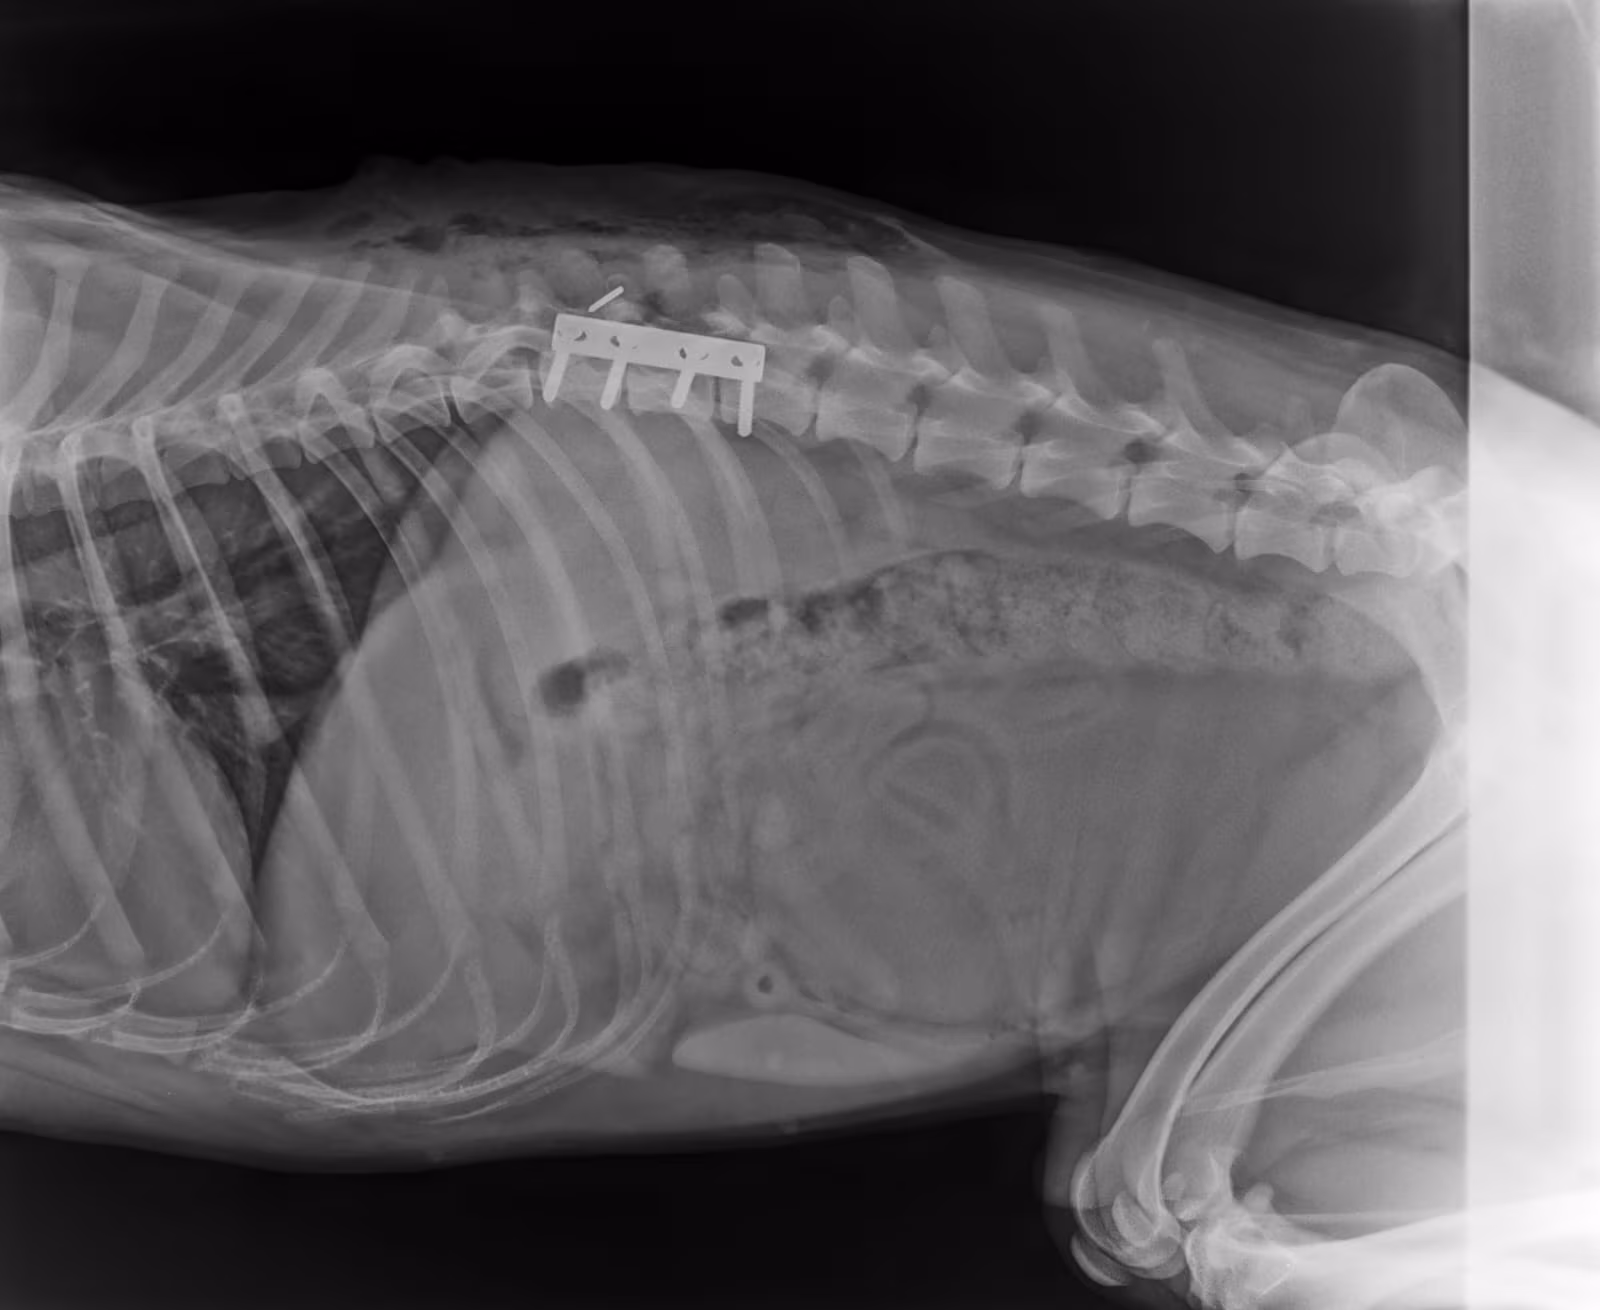

Es ist uns ein großes Anliegen, Euch den kleinen HOPE vorzustellen. Ein süßer, freundlicher kroatischer Schäferhund, der in seinem kurzen Leben schon unglaubliche Grausamkeiten erleben musste.

Sein ungebrochener Lebenswille beeindruckt uns jeden Tag – und er liebt die Menschen trotz seiner Vergangenheit nach wie vor.

Trotz aller Fortschritte benötigt HOPE weiterhin intensive Pflege. Laufende Tierarztbesuche, Windeln, Spritzen und weitere medizinische Maßnahmen sind notwendig. Wir freuen uns über jeden einzelnen Euro, den Ihr spendet, um HOPEs Leben zu verbessern und ihm endlich ein dauerhaftes Zuhause zu ermöglichen.